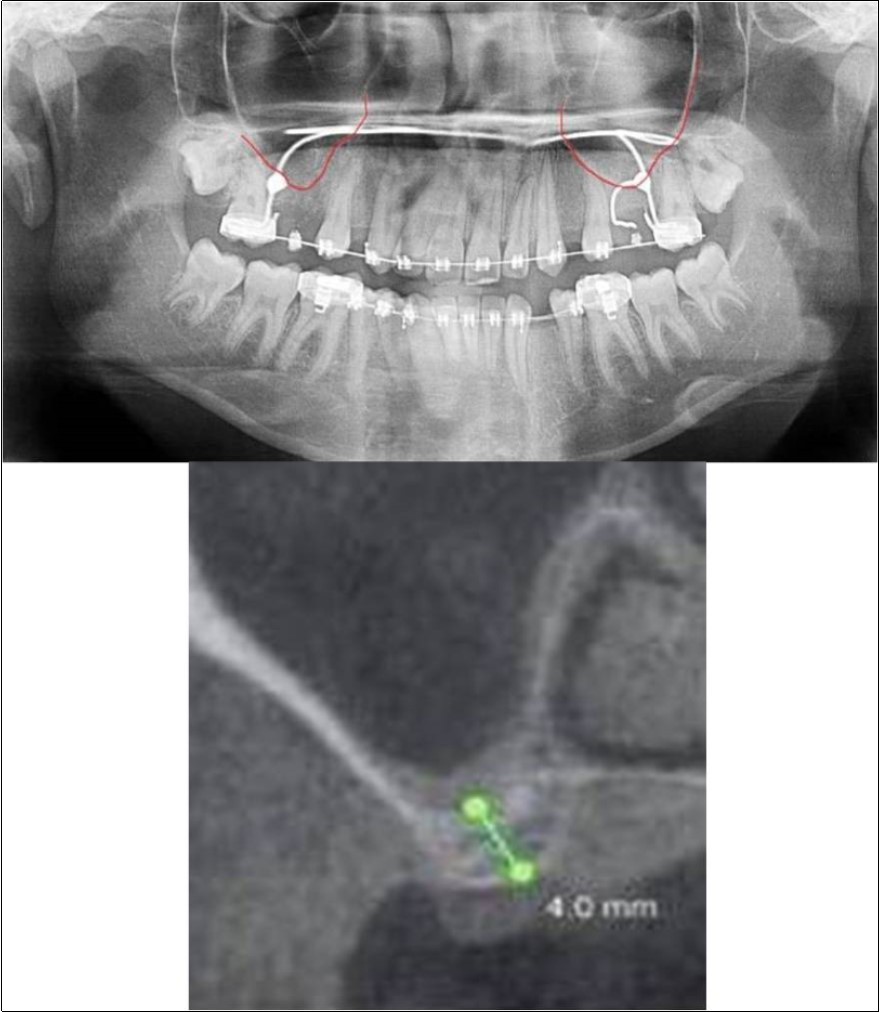

Figure 13.(a,b) Pre-treatment OPG and cross section of CBCT showing residual alveolar bone height for Case No.4;

Case Report 4:

A 19 years old young female patient reported to the Department of Oral and Maxillofacial Surgery, D.A.P.M.R.V Dental College and Hospital seeking options for replacement of her missing right and left upper first molars with a fixed prosthesis as she was uncomfortable with the removable partial denture i.r.t 16 and 26. The teeth were extracted 6 months ago because of gross loss of crown structure and poor prognosis for root canal treatment. Patient was also undergoing fixed orthodontic treatment for proclined upper anteriors. Patient did not give history of any existing sinus pathologies. All possible rehabilitative options were explained to the patient and a treatment plan of replacement of missing teeth with implant supported prosthesis using two dental implants was finalized.

Clinical and Radiological Assessment:

1.Partially edentulous maxillary arch with missing 16 and 26;

2.Increased pneumatisation of right and left maxillary sinus;

3.Height of available bone-

16 region: 6.5mm;

26 region: 6.2mm;

4.Transverse thickness of available bone (CBCT evaluation)-

16 region: 8.3mm;

26 region: 10.5mm;

5.Fixed orthodontic appliance;

6.Inter-ridge space adequate to place implant (11mm).

Treatment:

Patient underwent the procedure of indirect sinus elevation using sinus osteotomes in relation to 26 region. Calcium phosphosilicate putty was dispensed as the graft material through the crestal osteotomy site to maintain the elevated sinus membrane followed by placement of 5 x 10mm dental implant under local anaesthesia and strict aseptic protocols. The implant was allowed to osseo-integrate for a period of six months during which the patient was followed-up periodically and was assessed for peri-implantitis, crestal bone loss and mobility. Patient was taken-up for direct sinus elevation via lateral window approach for sinus augmentation i.r.t 16 region. Under aseptic conditions and local anaesthesia, lateral wall of maxilla was exposed after muco-periosteal flap elevation. A window was created of 1cm diameter corresponding to apical aspect of 16. Sinus membrane was identified and elevated using sinus elevators and reamers without perforating the lining. Once the sinus membrane was elevated, phosphosilicate putty was dispensed through the lateral osteotomy site as the graft material to achieve an augmentation of 1cm assessed clinically and confirmed using post-operative OPG. At the end of 6 months, a repeat CBCT scan was advised to evaluate the increase in bone height. (Figure 13a,b, pre-treatment; Figure 14a,b, post-treatment)